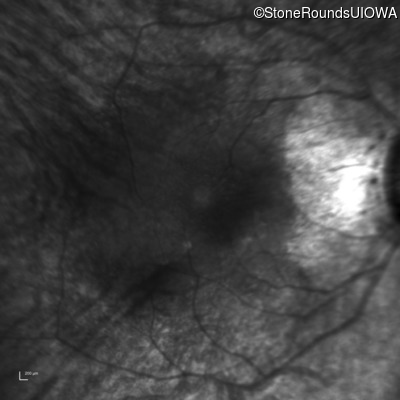

Infrared Fundus Photograph - Right - 20/50

Exemplar